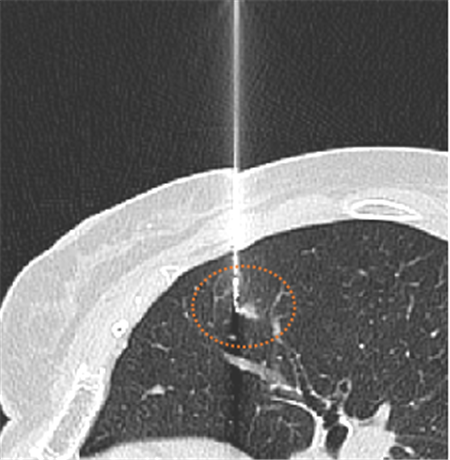

CT引导下肺小结节术前辅助定位就成为了有效的手段。在临床使用中安全可靠、成功率高、并发症少,可为临床医生在术中快速准确探寻结节位置、最大限度精准切除肿瘤,并给病理科医生提供精准的切片范围,不仅缩短了患者手术时间、降低手术风险,而且可较大限度保护患者肺组织、肺功能。目前,玉溪市人民医院已成功的进行了多例CT引导下肺结节穿刺术前定位,穿刺过程顺利,手术成功。

CT呈像浸润性腺癌引导定位

据了解,玉溪市人民医院医学影像部现已常规开展CT引导下经皮穿刺肺小结节辅助定位及活检手术,发现早期肺癌,避免患者因发现较晚发生转移而遭受放化疗的痛苦,提高生活质量,提高患者生存率。同时,这项技术的推广应用也可更好的为玉溪及周边地区的体检客户及患者做好肺结节的筛查及诊断工作。